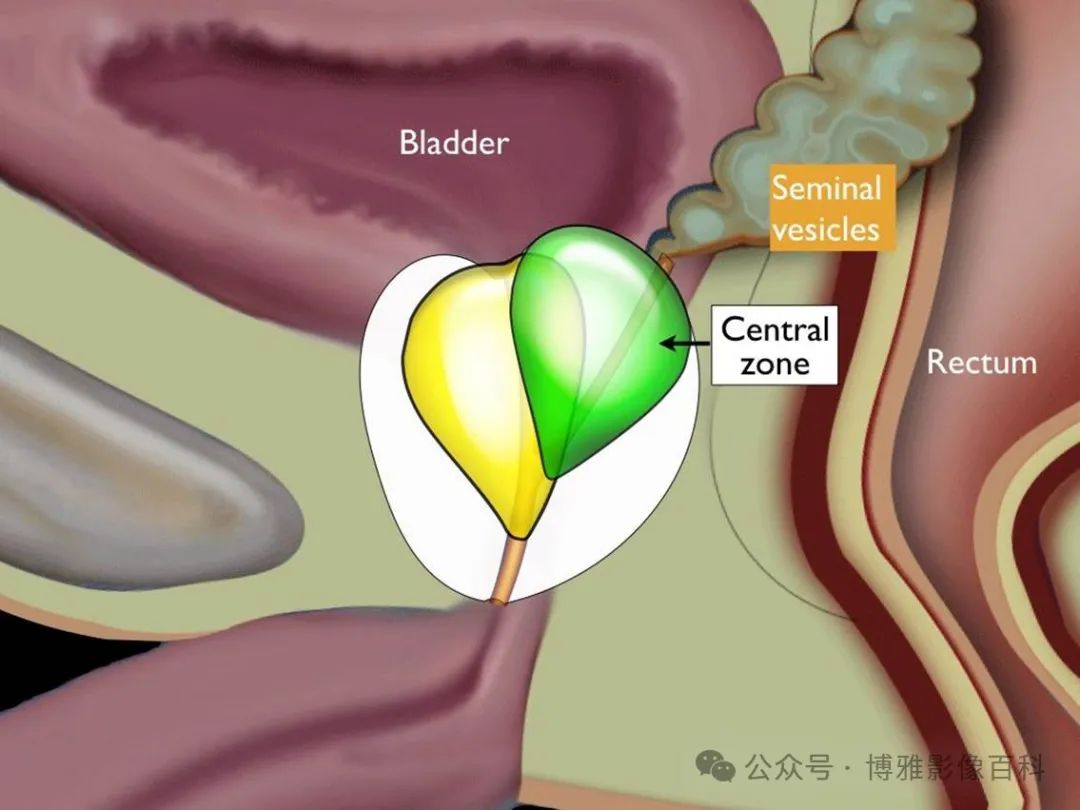

前列腺分区解剖学

25% 的前列腺癌起源于移行带 (TZ)。极少数前列腺癌出现在中央带或前纤维肌基质中。